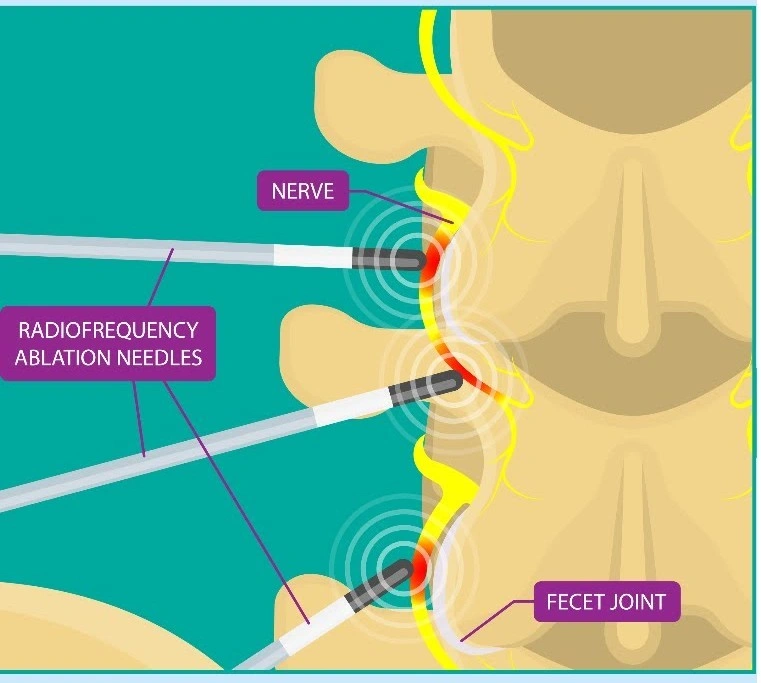

Nerve Blocks / Ablation / Neurolysis

What are Nerve Blocks?

Nerve blocks involve injecting medication around specific nerves to interrupt pain signals sent to the brain.

Other Techniques

Nerve Ablation – Using heat or energy to disable pain-causing nerves

Neurolysis – Destroying problematic nerves that cause chronic pain

Conditions Treated

Chronic joint pain

Back and neck pain

Nerve-related pain syndromes